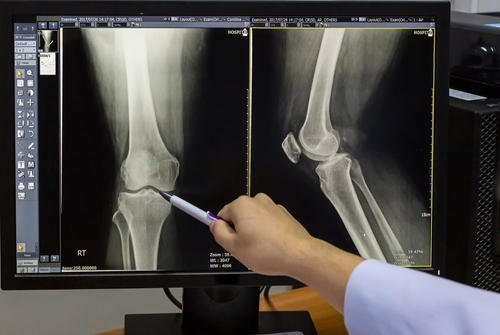

Фотогалерея

После процедуры рентгенолог начинает анализировать полученную информацию и сравнивать ее с нормальными показателями. В своем отчете он указывает состояние костей, их целостность и контуры, описывает ширину суставной щели, суставные поверхности. Помимо этого, доктор отражает обнаруженные патологии и их параметры: вид, локализация, форма, распространенность, связь с рядом расположенными структурами. В конце врач пишет заключение.

Основным инструментальным методом диагностики перелома костей является рентгенография. Процедура позволяет быстро выявить нарушение целостности костных структур и в кратчайшие сроки приступить к нужному лечению. На рентгенограмме можно увидеть место повреждения и его характер, расположение костных фрагментов. Признаками перелома является расхождение, смещение костей, изменение суставной полости.